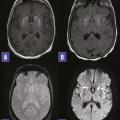

Striatopathie diabétique

COMPLICATIONS DU DIABETE

HYPERGLYCEMIE

Image